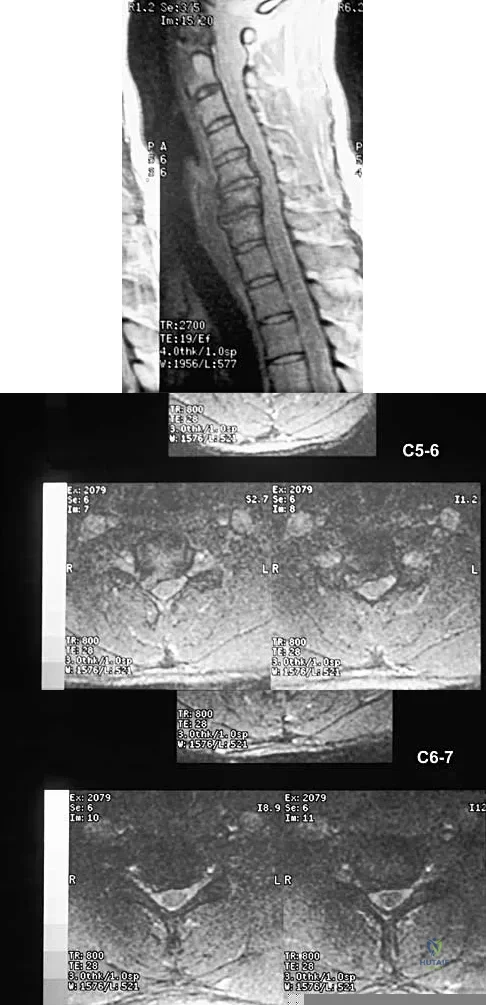

Question 33High Yield

A 40-year-old carpenter has a 3-month history of right arm pain and neck pain that now leaves him unable to work. Examination reveals a positive Spurling test, weakness of the biceps, and a mildly positive Hoffman's sign on the right side. Electromyography and nerve conduction velocity studies show a right C6 deficit. Figures 27a through 27c show MRI scans that reveal two-level spondylotic disease at C5-6 and C6-7, a large herniated nucleus pulposus at C5-6, and a prominent ridge and hard disk at C6-7. Nonsurgical management fails to provide relief, so the patient elects surgical intervention. Which of the following surgical options would give the best long-term results?

Explanation